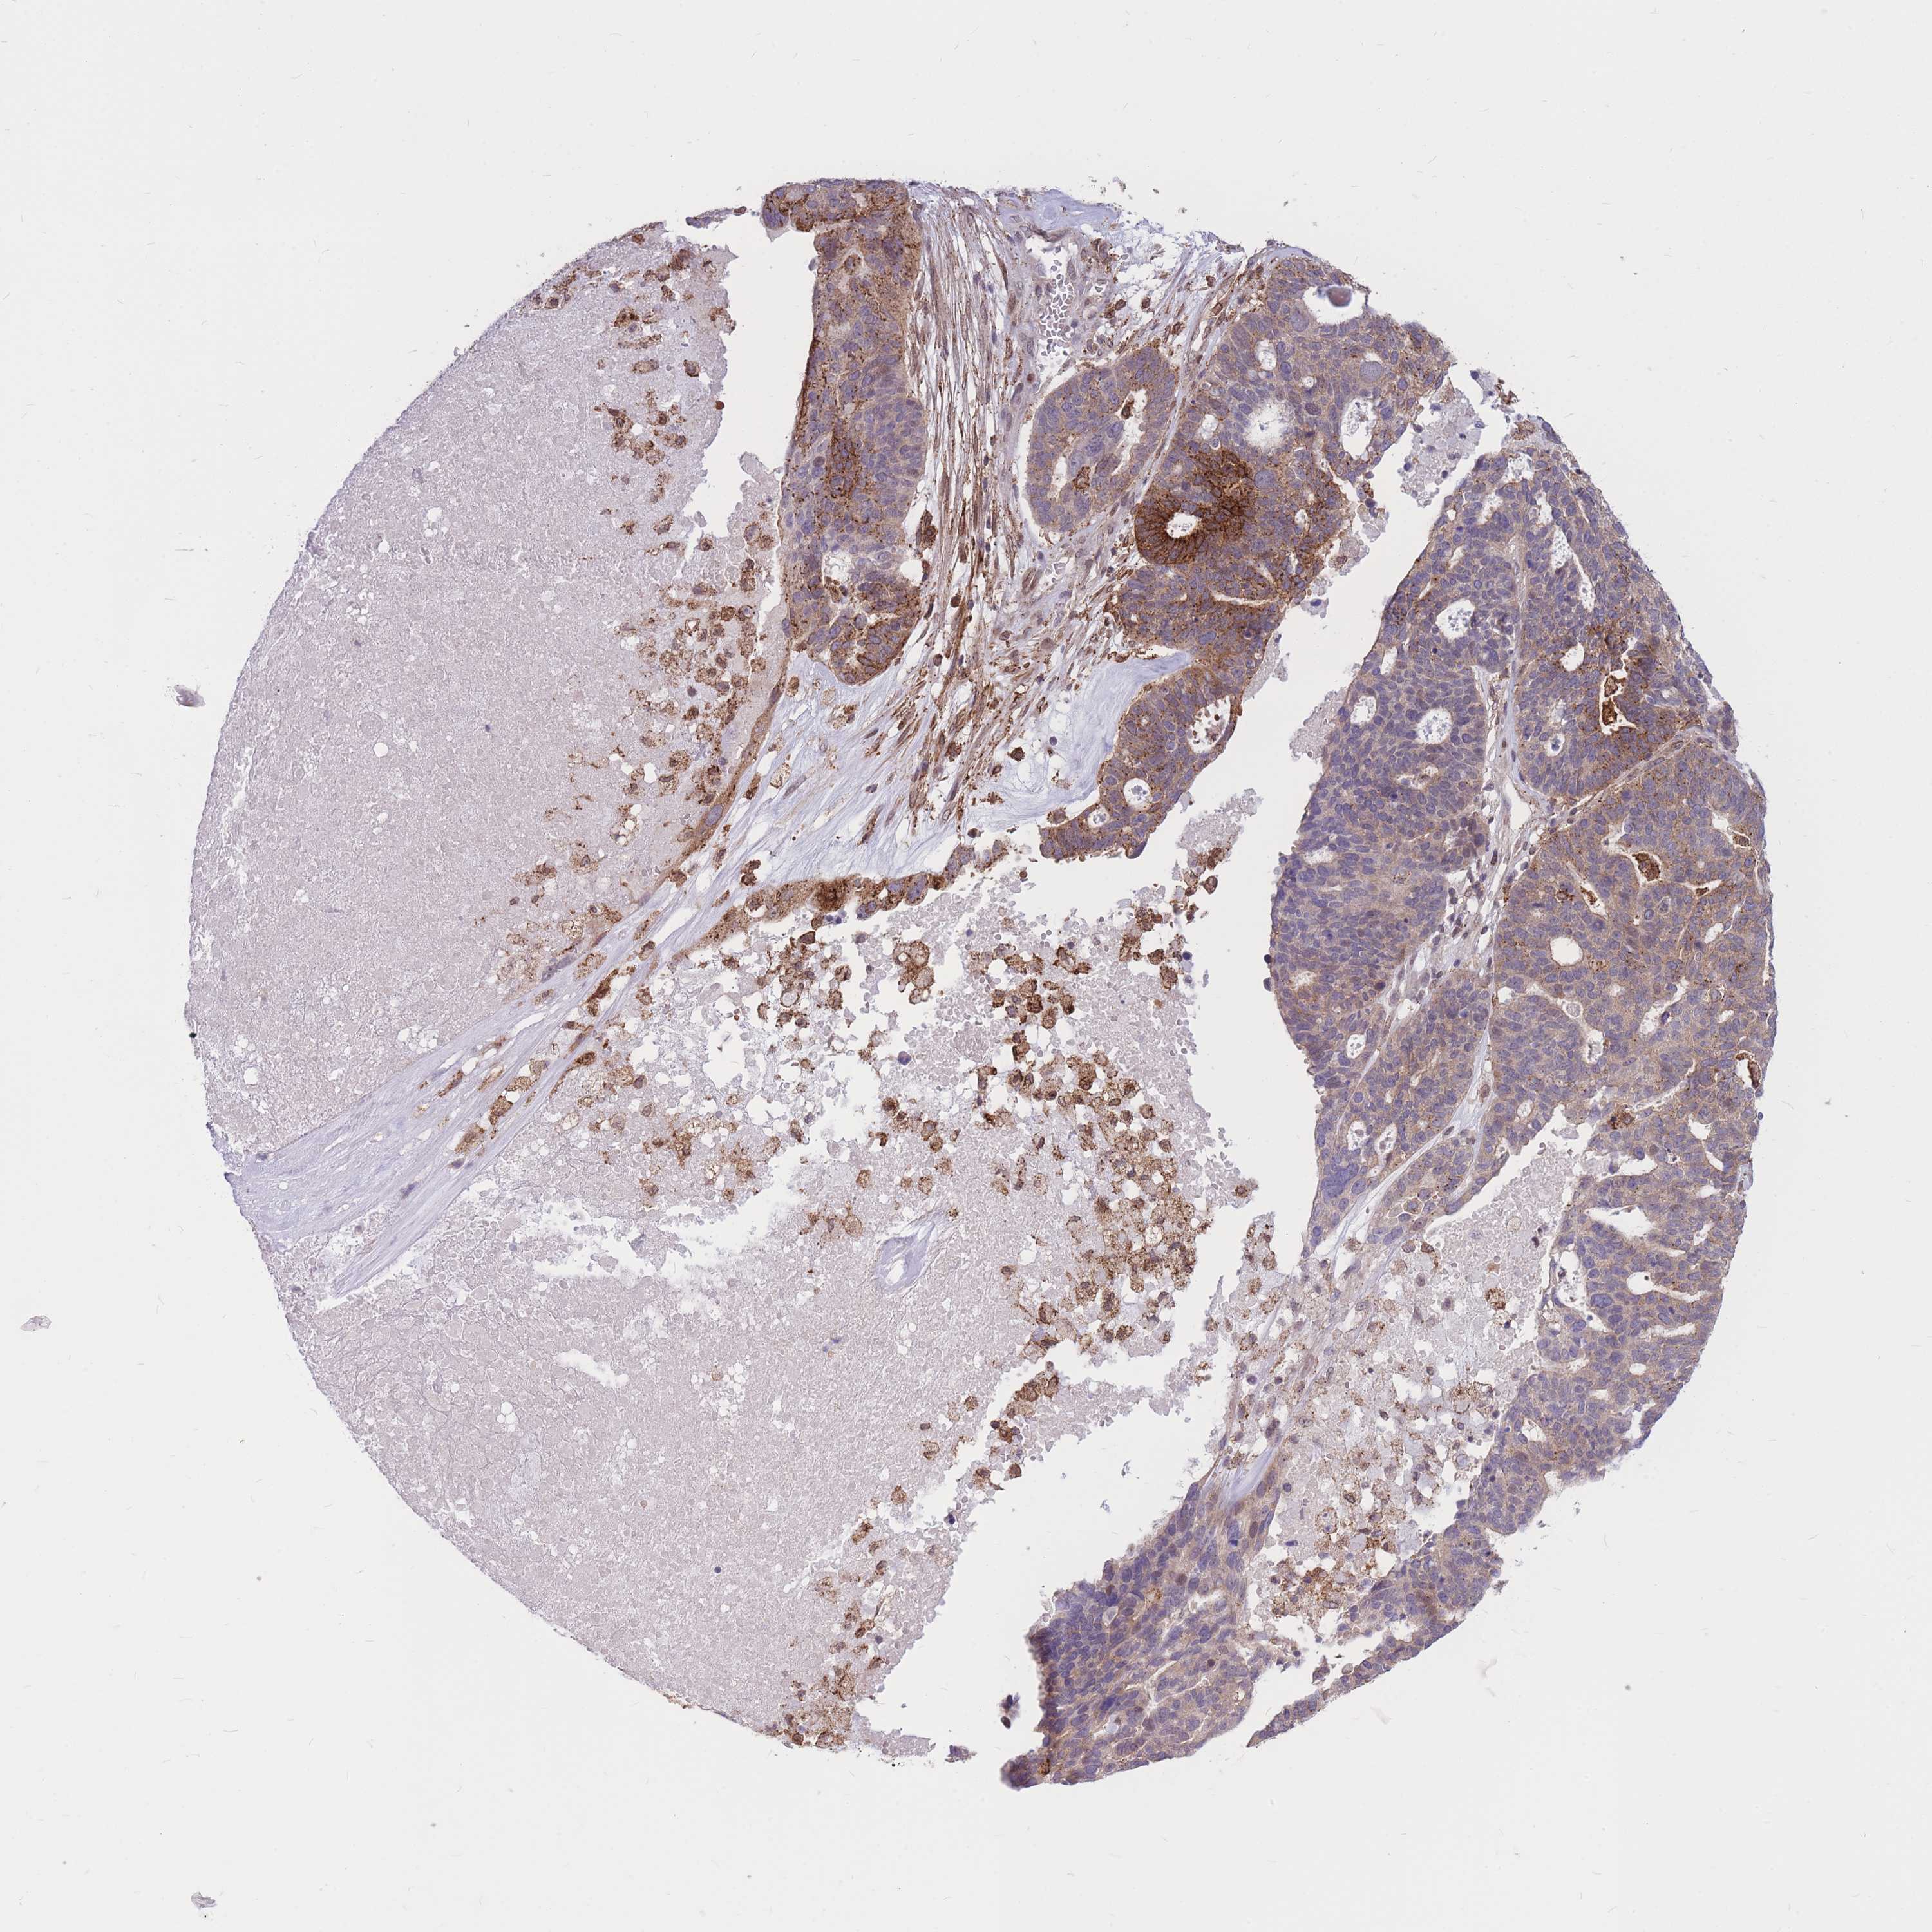

OVARIAN CANCER - Protein expressioni

A mouse-over function shows sample information and annotation data. Click on an image to view it in a full screen mode. Samples can be filtered based on level of antibody staining by selecting one or several of the following categories: high, medium, low and not detected. The assay and annotation is described here.

Note that samples used for immunohistochemistry by the Human Protein Atlas do not correspond to samples in the TCGA dataset.

Antibody stainingi

Antibody staining in the annotated cell types in the current human tissue is reported as not detected, low, medium, or high, based on conventional immunohistochemistry profiling in selected tissues. This score is based on the combination of the staining intensity and fraction of stained cells.

Each image is clickable and will lead to virtual microscopy that enables deeper exploration of all samples and also displays staining intensity scores, fraction scores and subcellular localization as well as patient and tissue information for each sample.

Antibody CAB017849

Carcinoma, NOS

Cystadenocarcinoma, serous, NOS